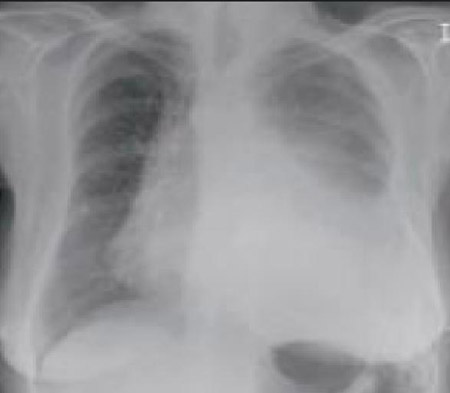

[Figure caption and citation for the preceding image starts]: A. Radiografia torácica portátil ortostática antes da aspiração; B. Radiografia torácica 1 hora após a aspiração, mostrando infiltrados alveolares difusos bilaterais, piores nas bases do lado direitoDo acervo pessoal do Dr. S. Murgu e do Dr. H. Colt, Universidade da Califórnia / Irvine Medical Center [Citation ends].